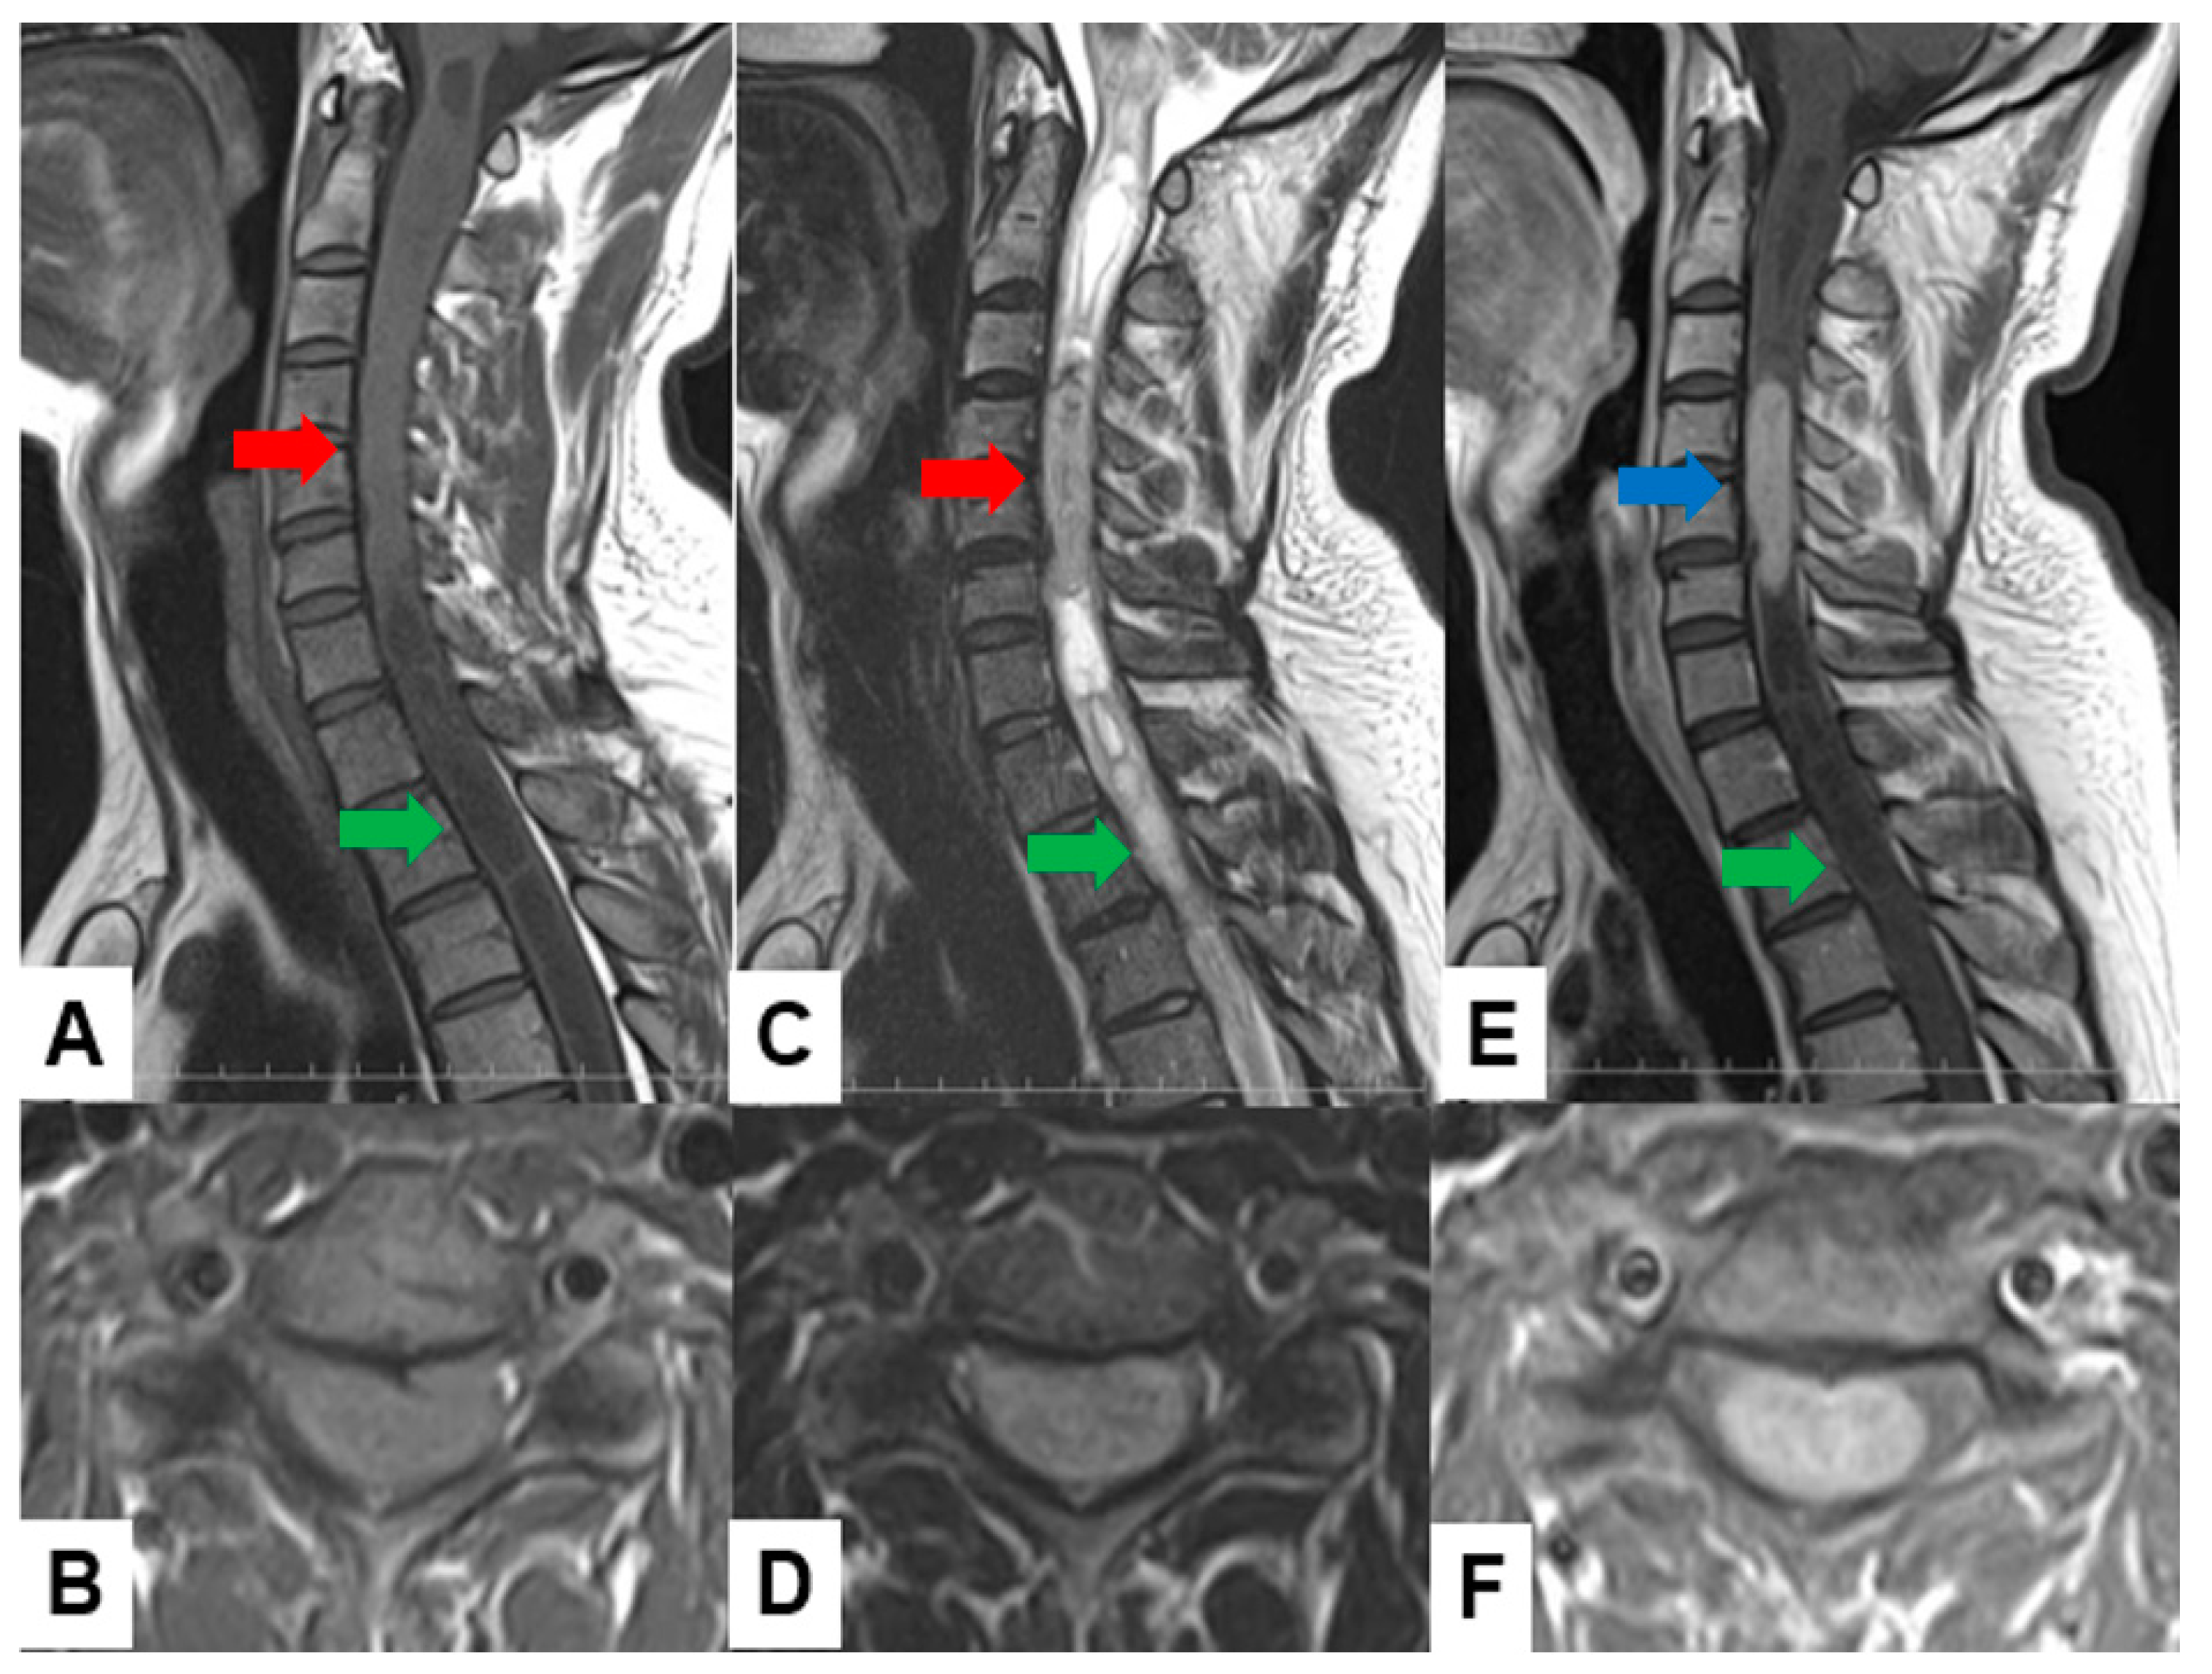

- Jung, J.S.; Choi, Y.S.; Ahn, S.S.; Yi, S.; Kim, S.H.; Lee, S.K. Differentiation between spinal cord diffuse midline glioma with histone H3 K27M mutation and wild type: Comparative magnetic resonance imaging. Neuroradiology 2019, 61, 313–322. [Google Scholar] [CrossRef] [PubMed]